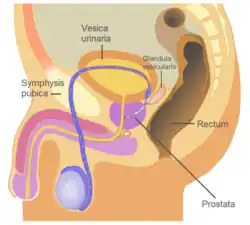

Die Prostata (von altgriechisch προστάτης prostátēs ‚Vorsteher‘, ‚Vordermann‘) oder Vorsteherdrüse ist bei allen männlichen Säugetieren zum einen eine akzessorische Geschlechtsdrüse zur Herstellung eines Teils der Spermaflüssigkeit und zum anderen ein Muskelkomplex zur Kanalumschaltung zwischen Blasenleerung und Ejakulation. Sie liegt beim Menschen unterhalb (bei Tieren entsprechend hinter) der Harnblase und umkleidet den Anfangsteil der Harnröhre bis zum Beckenboden. Sie gleicht beim Mann in Größe und Form einer Kastanie. An die Rückseite der Prostata grenzt der Mastdarm. Deshalb kann sie vom Enddarm aus mit den Fingern ertastet und beurteilt sowie in sexuellem Kontext auf diesem Weg durch Prostatamassage stimuliert werden.

Die Prostata liegt subperitoneal, das heißt unter (bei Tieren entsprechend hinter) dem Bauchfell. Sie ruht auf dem Diaphragma urogenitale und schmiegt sich von kaudal (beim Menschen unten, bei Vierfüßern hinten) an den Hals der Harnblase an. Dorsal (zum Rücken hin) wird sie durch den Mastdarm begrenzt, ventral (zum Bauch hin) durch die Schambeinfuge. Mit dieser ist sie durch ein Band, das Ligamentum puboprostaticum, verbunden. Durch die Mitte der Prostata verläuft die Harnröhre. Aus diesem Grund kann es bei einer krankhaften Vergrößerung der Prostata zu Problemen beim Wasserlassen bis hin zum Blasenverschluss kommen.